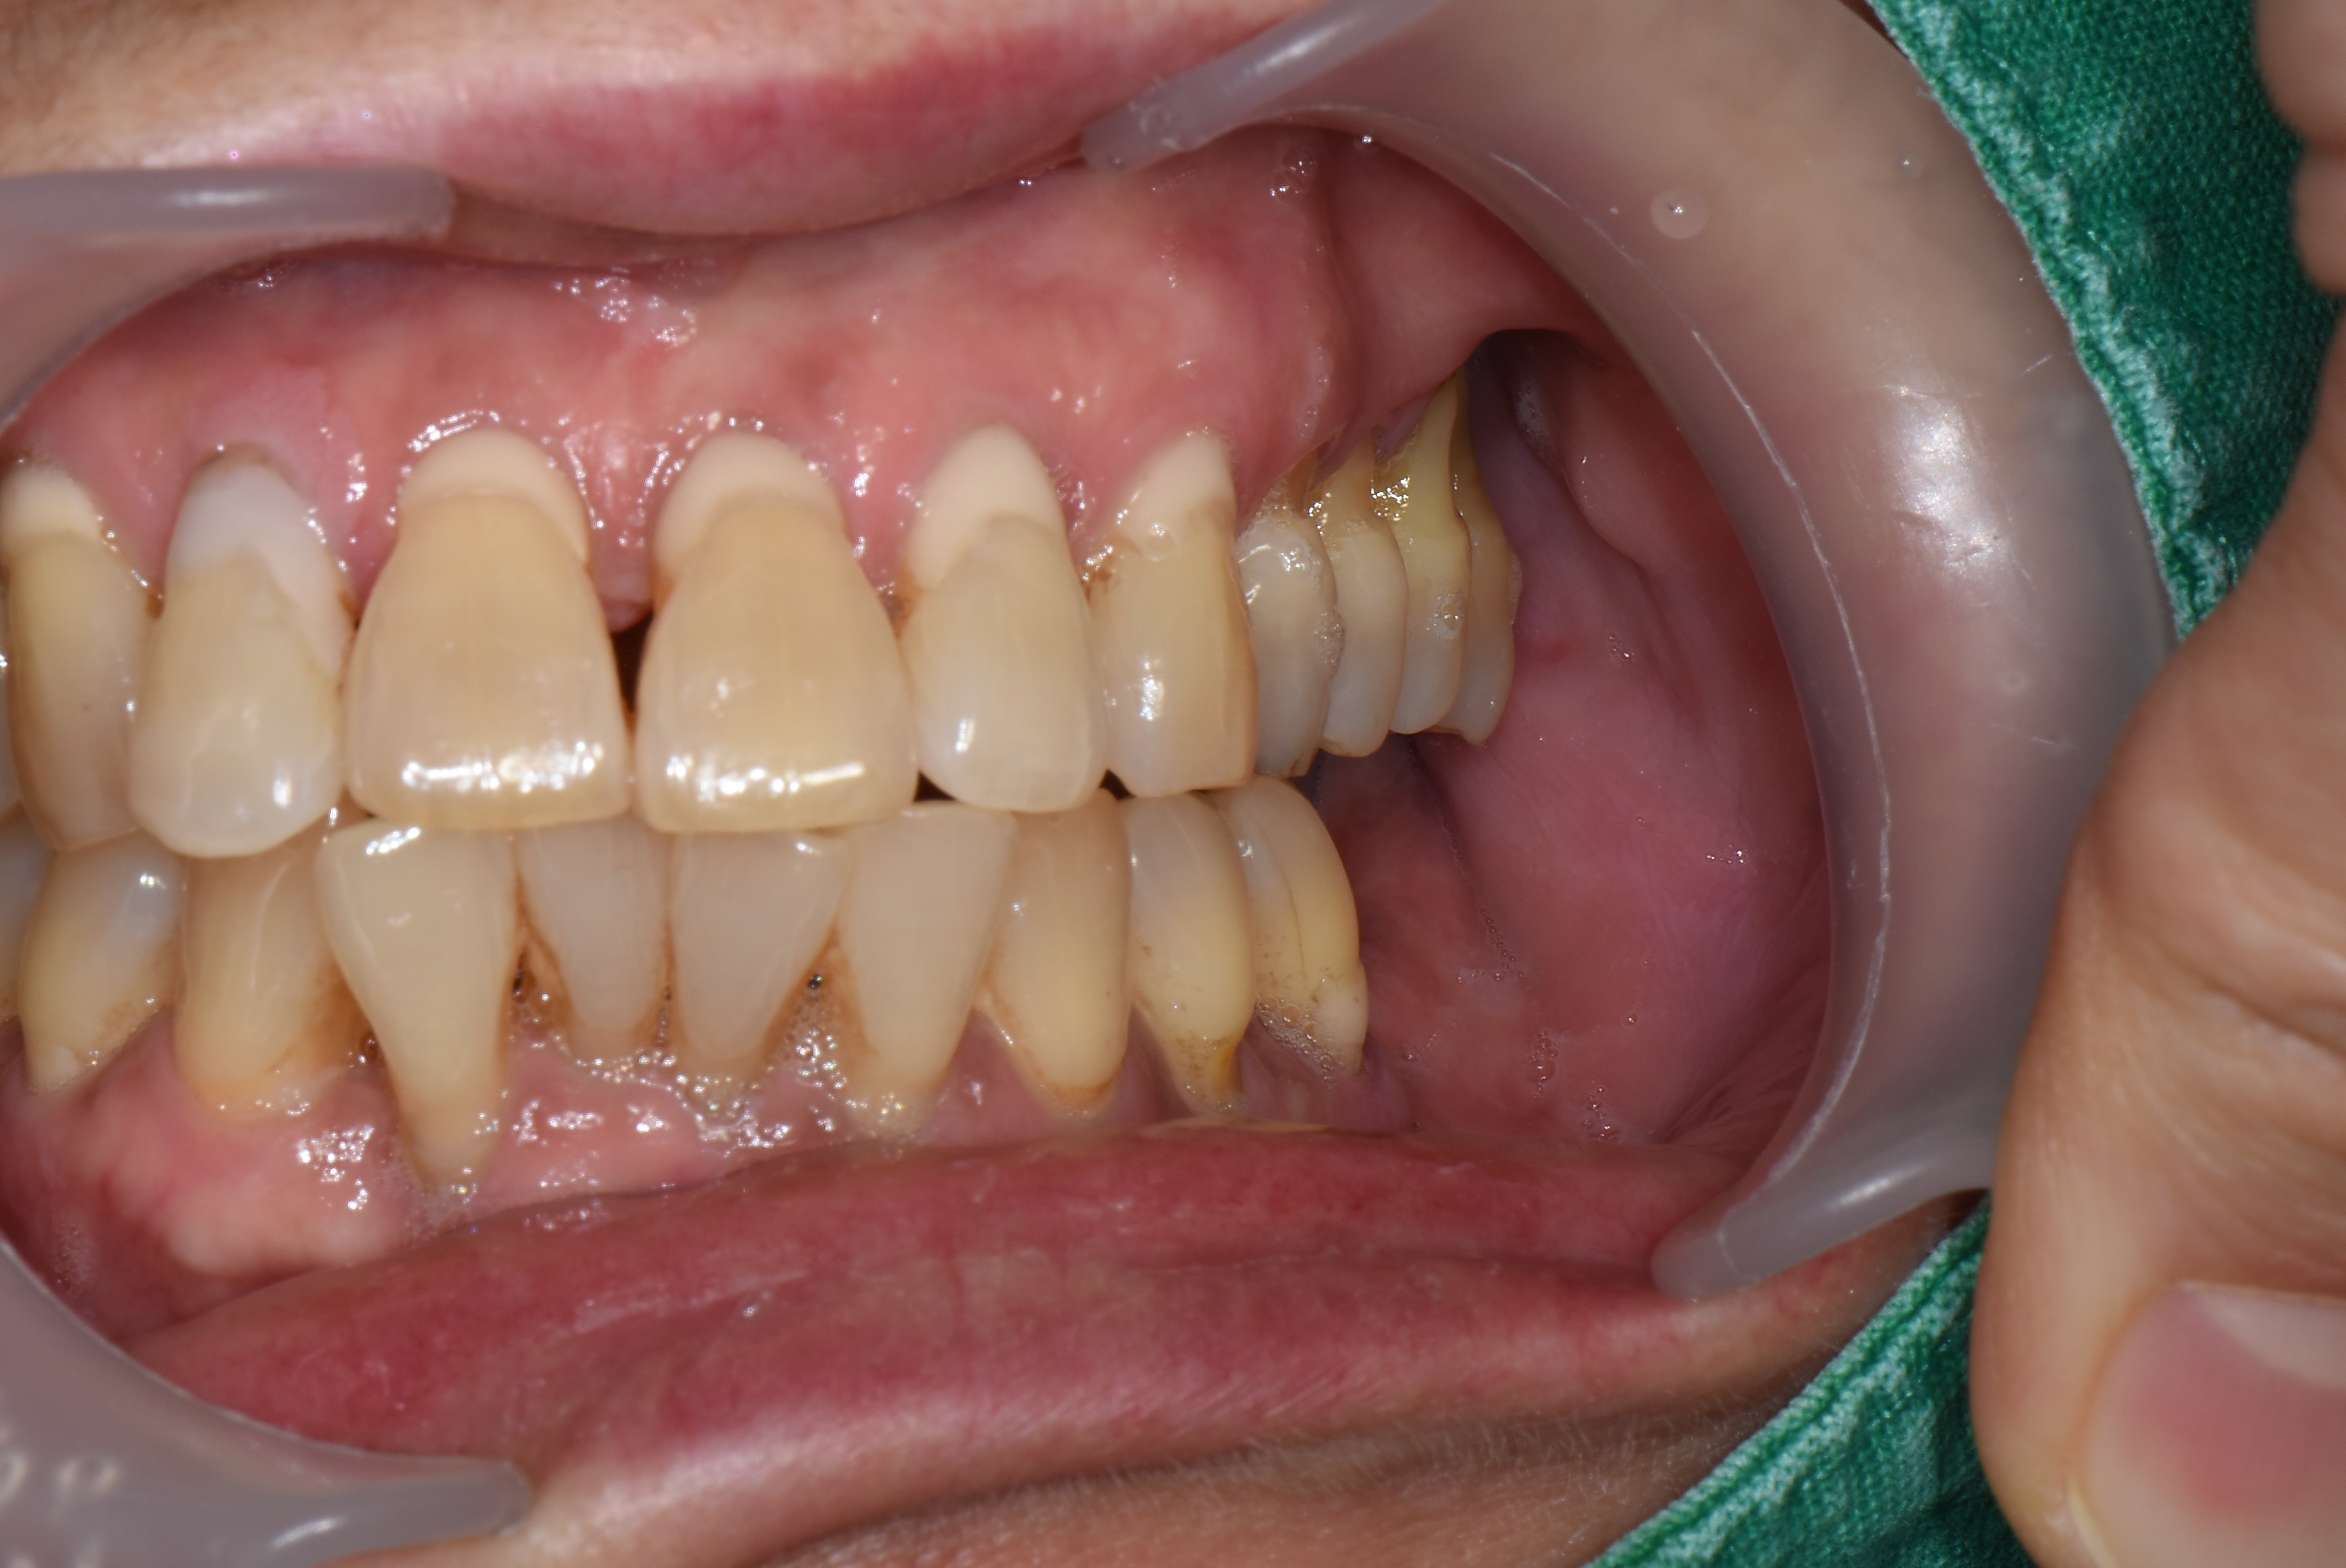

오랜 기간 아래 어금니가 없이 지내셨던 50대 여성분이 김포 서울케이치과에 내원 하셨습니다.

검진을 해보니 위에 양쪽 어금니가 많이 내려와 있고 치주염이 심하여 흔들리고 있었습니다.

치아를 살리기에는 이미 늦은 상태로 발치 후 임플란트로 치료 계획을 세웠습니다.

<처음 상태>

파노라마 엑스레이와 구내 사진에서 보듯이 위에 양쪽 어금니는 모두 발치가 필요한 상태입니다.